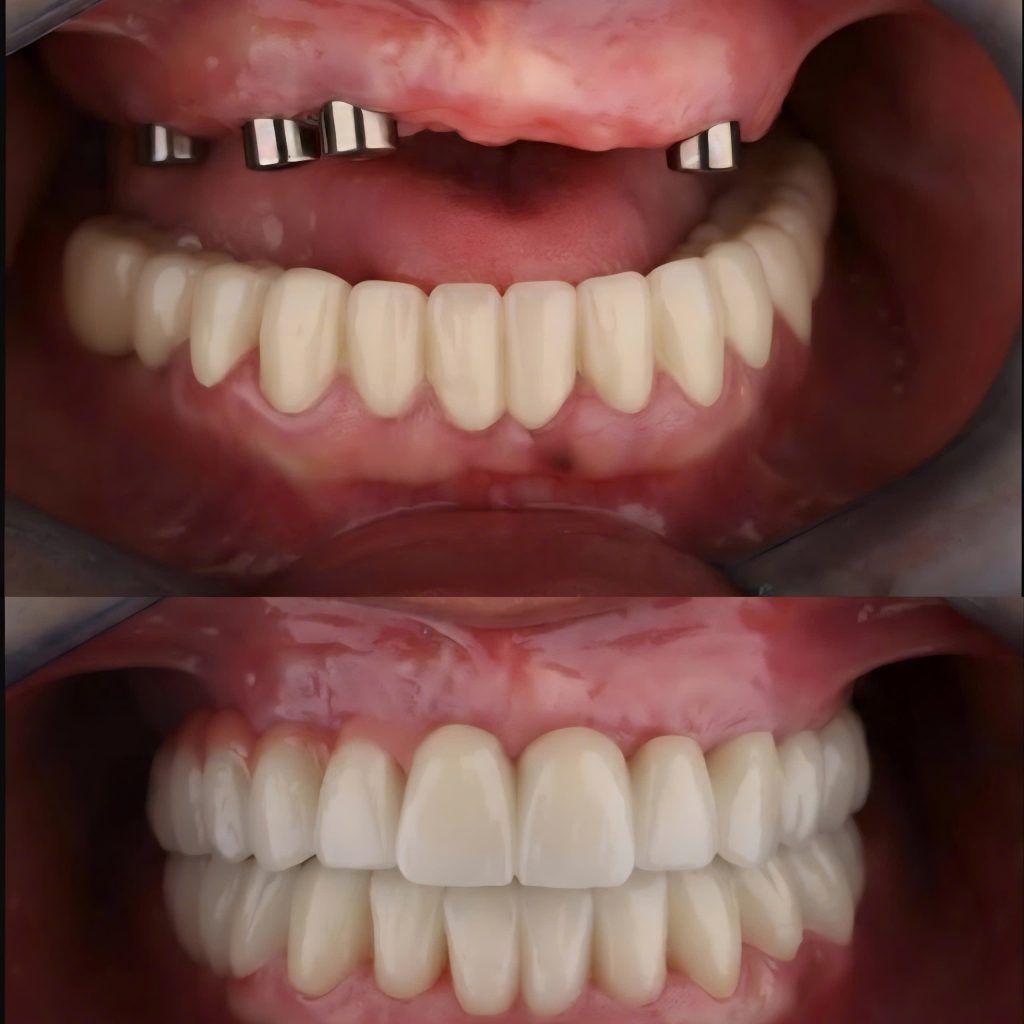

Cùng tìm hiểu quy trình cấy ghép Implant an toàn tại Nha Khoa Ace Smile qua trải nghiệm thực tế của anh Cường.

Bước 6 – Hoàn tất phục hình